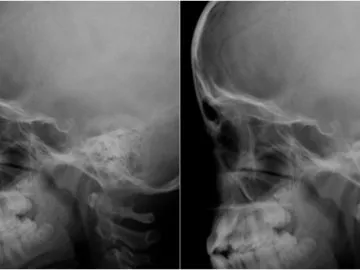

Sin embargo, al intentar limpiar la zona afectada, los profesionales se encontraron con un cuadro mucho más grave del esperado: la infección llevaba varias semanas avanzando y las larvas habían comenzado a destruir tejido blando e incluso perforado parte del hueso del cráneo.

Según explicó el pediatra Flavio Serra, el caso corresponde a una miasis foruncular, una enfermedad provocada por moscas que depositan huevos en la piel. "Las larvas se desarrollan dentro del tejido y pueden generar lesiones profundas. En este caso ya había compromiso óseo", detalló el médico a El Litoral.